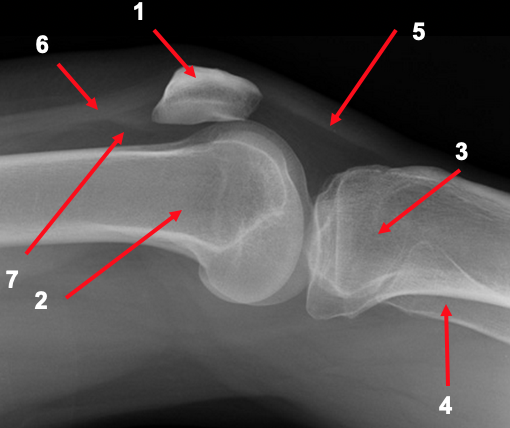

What is shown in the lateral knee radiograph?